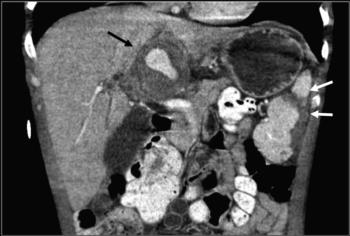

Figure 3. 36-year-old man with infective endocarditis associated with IV-SUDs. On the coronal contrast-enhanced abdominal CT image, there is a hepatic hilum hypervascular mass (black arrow) compatible with a hepatic artery mycotic aneurysm. There is also a splenic infarct (white arrows) secondary to disseminated septic emboli.

High-res (TIF) version